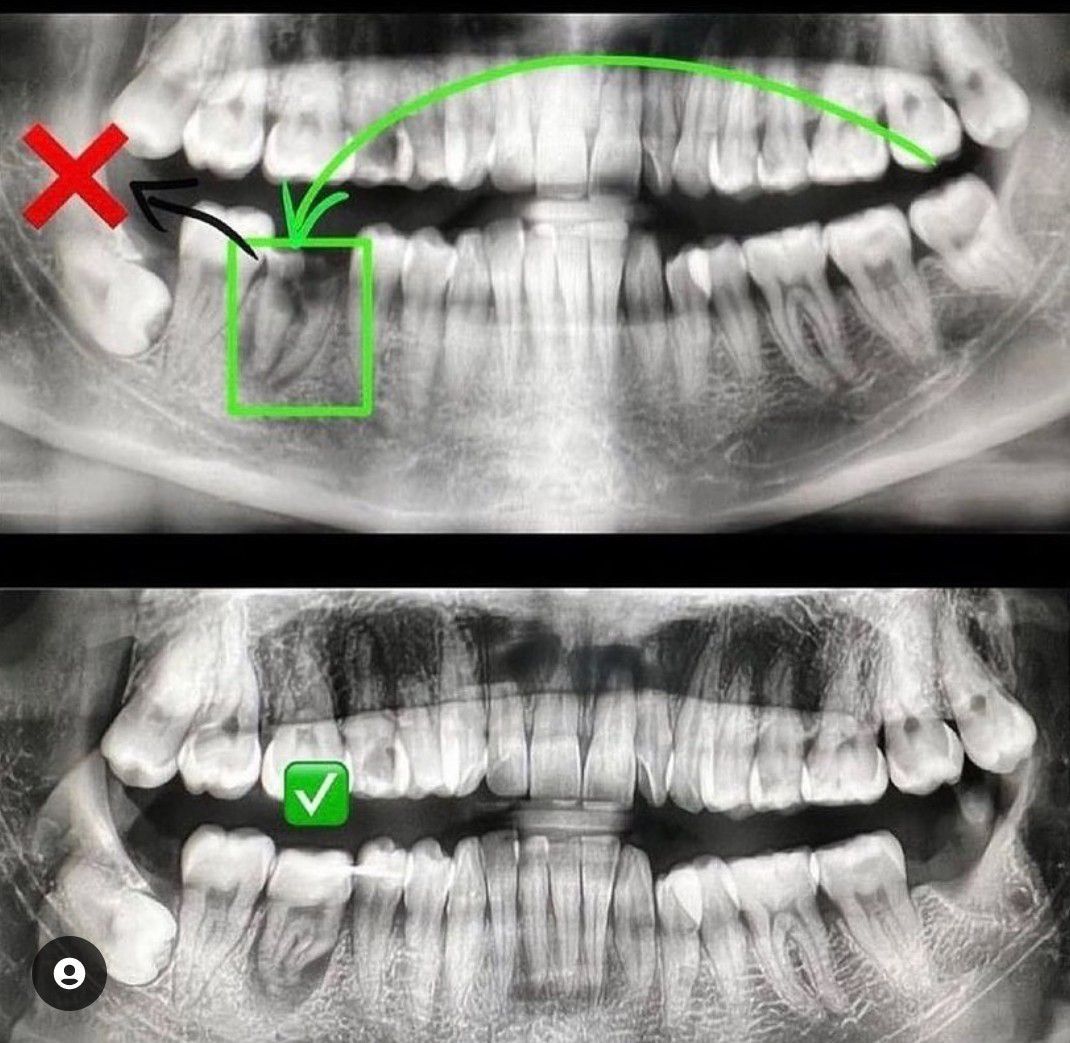

Autotransplantation is the transplantation of one's own tooth, unimportant for the bite and chewing process ("eight" or wisdom tooth), instead of a destroyed tooth that cannot be restored. In this clinical situation, tooth 46 is severely damaged. Treatment protocol: 1. Removed 46 tooth. 2. Cleaned the hole. 3. Removed tooth 38 and transplanted instead of 46 tooth. 4. Splinted on the adjacent tooth. Next stage: ✅After 2 weeks we remove the nerve and put Ca + for 2 weeks. ✅After 2 weeks we carry out obturation. We put a crown on this tooth and complete the treatment. ✳️ Another thing to consider is TIME. You will need to have time to transplant the extracted tooth within 18 minutes.